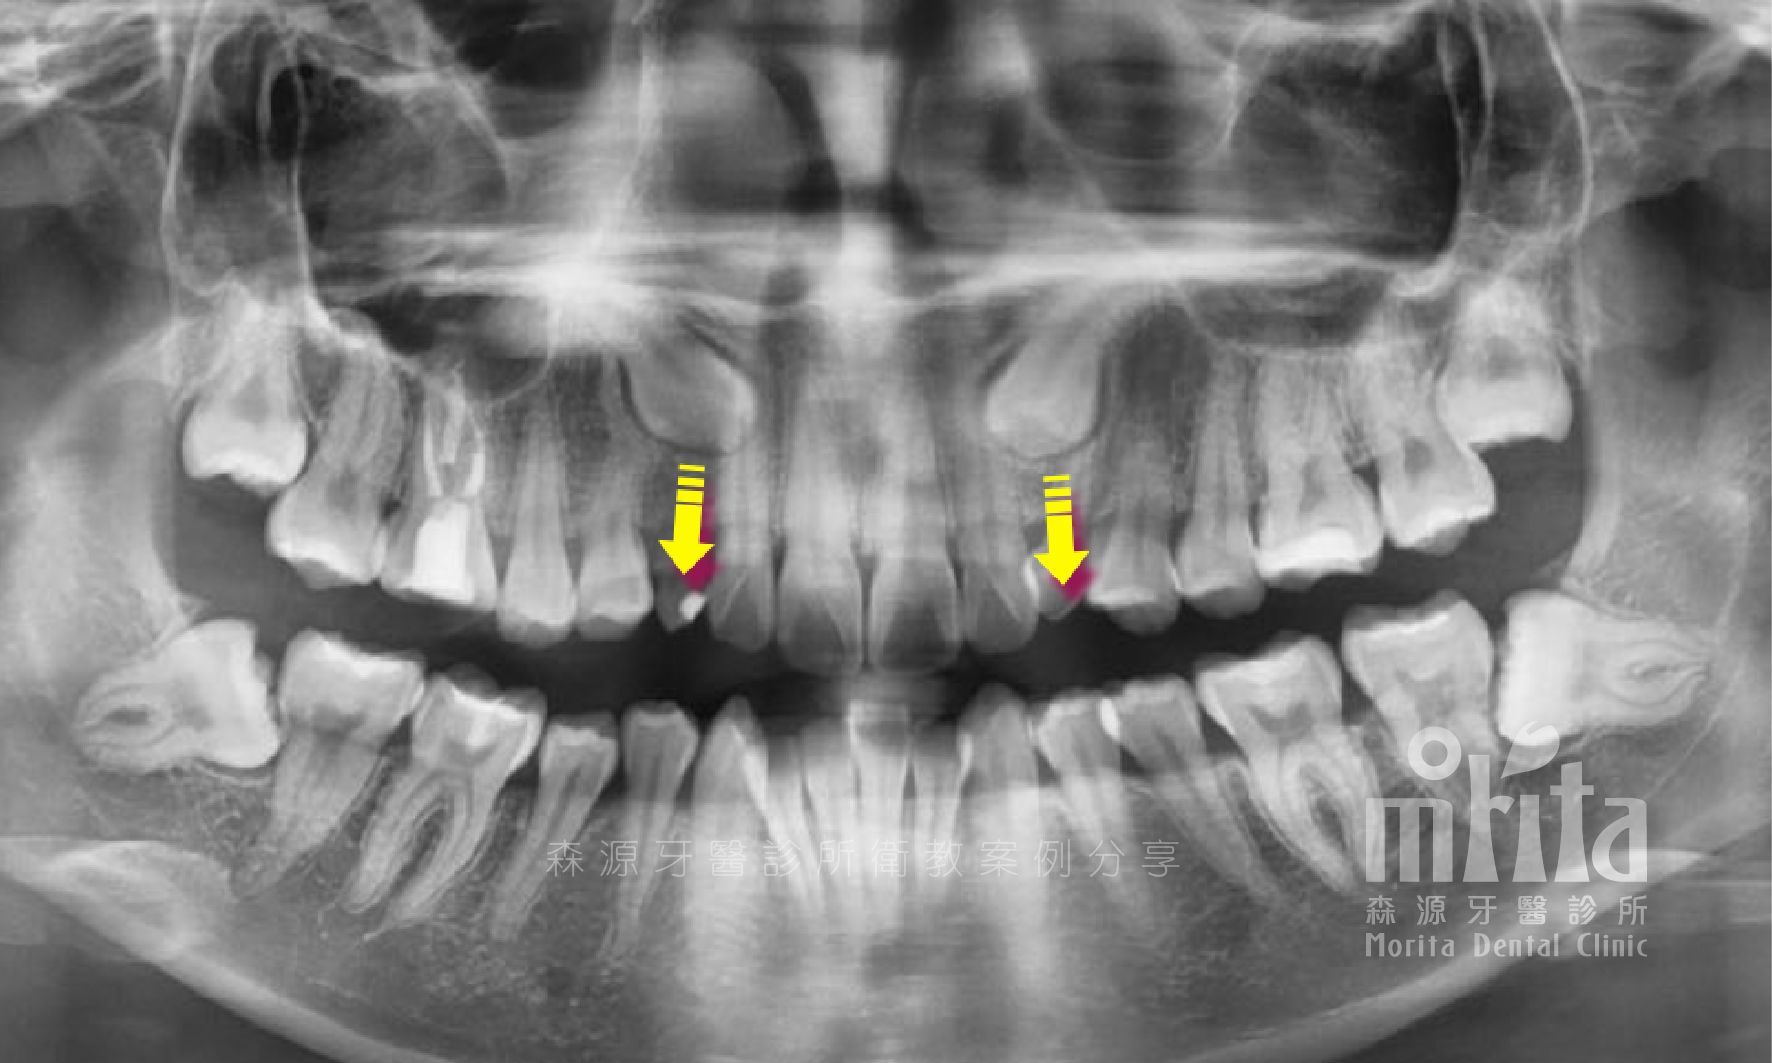

阻生齒 Impaction

犬齒是上顎恆齒中較晚萌發的牙齒,常常會因為被鄰近牙齒佔據的生⻑空間而無法順利萌發,困難的阻生齒常常會需要藉助手術露出,以及搭配特殊裝置,才有機會順利拉出。